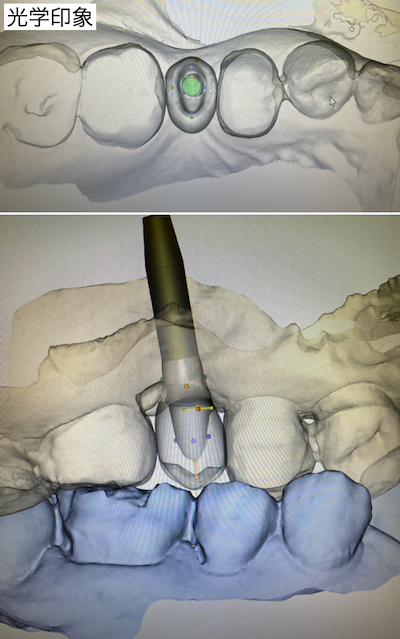

以前CTを撮影していたので、それを元に手術計画書も合わせて作成しました。

患者さんはインプラント治療をご希望されたので、インプラント手術を行うこととなりました。患者さんは15:30にご来院されて、局所麻酔、クリーニングを行い、16:00に手術開始、16:20に縫合終了。術後の資料採取を行い、資料を見ながら術中の説明、術後の注意事項を説明し16:30には医院を出られました。

インテグレーションを待つ2ヶ月の間に、両隣在歯のセレック治療を行いました。その後、2次手術を行い、仮歯を適合させました。リハビリ後に光学印象を行いました。

自身のインプラント埋入の再評価を行い、補綴物の設計を行いました。1週間後にカスタムアバットメントとセラミックを装着しました。